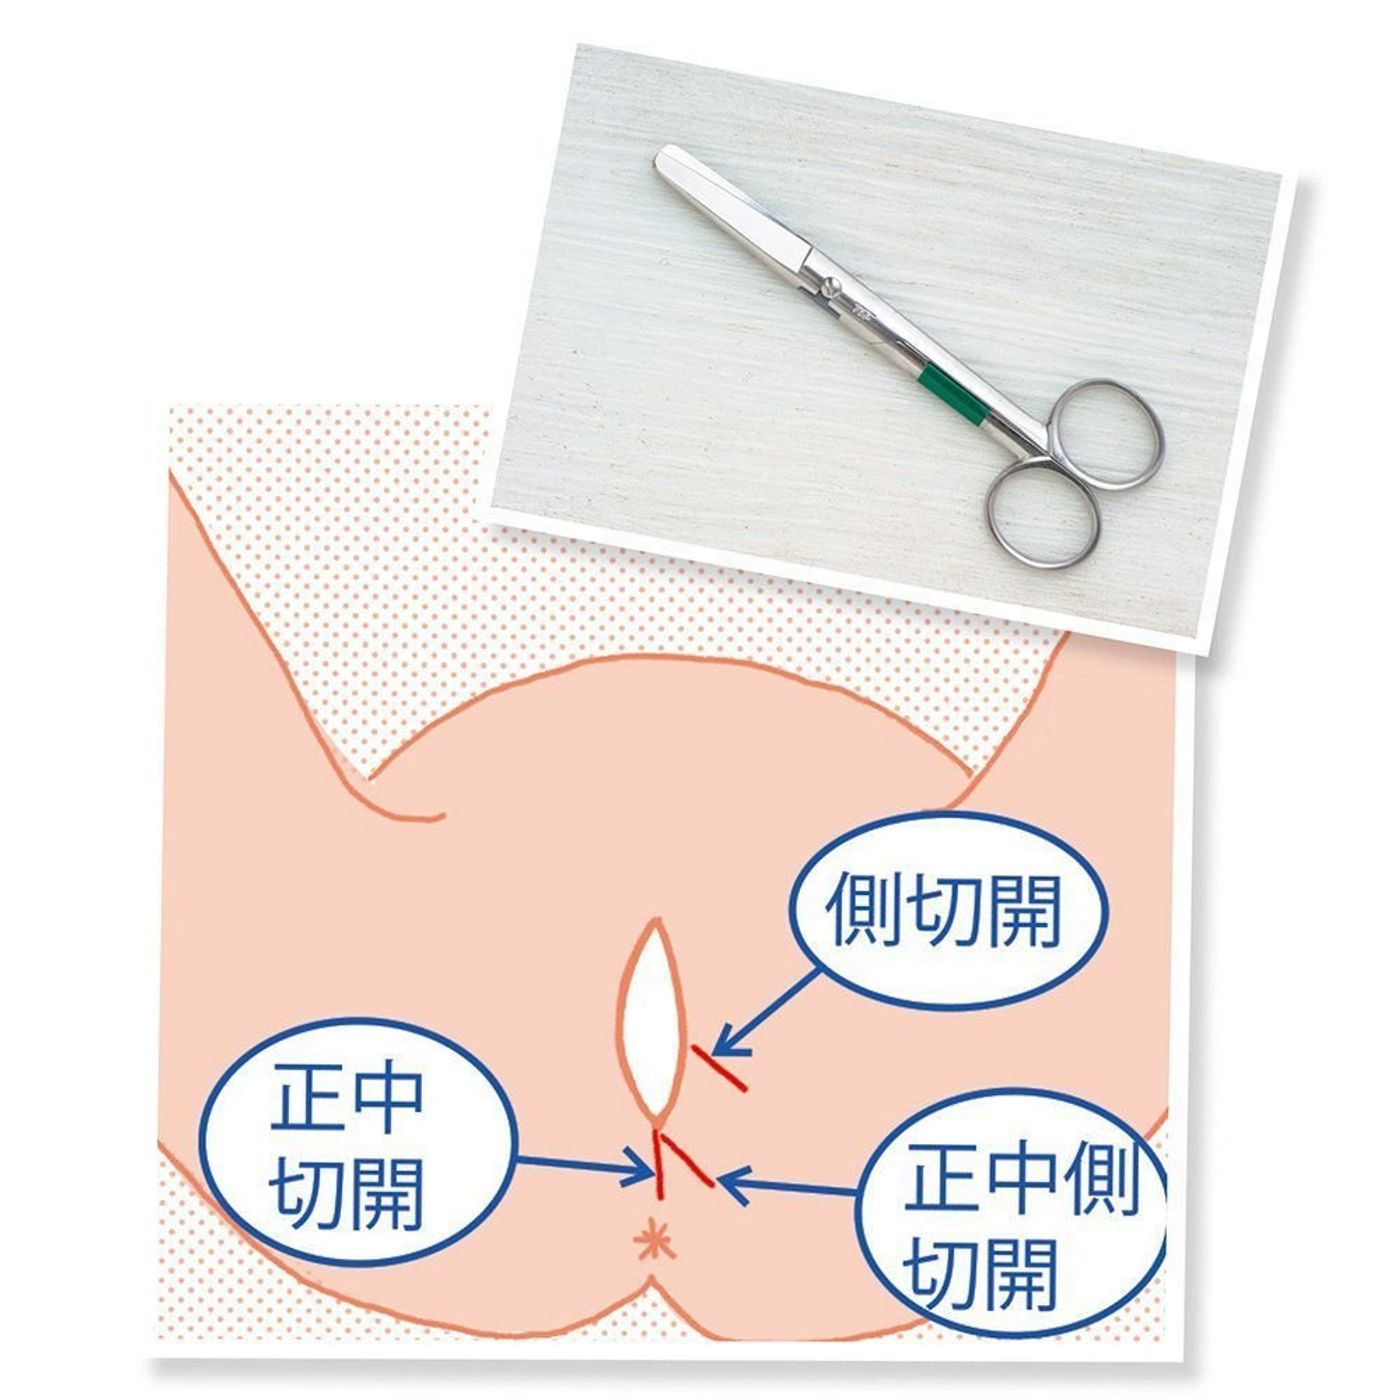

会陰切開について東京・世田谷での出産・分娩なら国立成育医療研究センター 産科。

会陰切開 をするタイミングは?痛みはある?切らない人もいる?会陰切開の不安と疑問に産婦人科医がお答えBaby-mo ベビモ。

会陰切開、吸引・鉗子分娩 出産のときの大切な医療処置たまひよ。

会陰切開 をするタイミングは?痛みはある?切らない人もいる?会陰切開の不安と疑問に産婦人科医がお答えBaby-mo ベビモ。

会陰切開、吸引・鉗子分娩 出産のときの大切な医療処置たまひよ。

出産時に行われる会陰切開の可能性を示す図」のベクター画像素材 ロイヤリティフリー200938991Shutterstock。